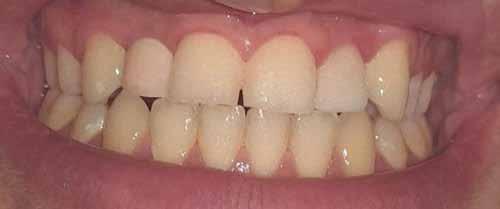

The inclusion criteria were patients within 20 to 40 years with unrestorable bilateral teeth with a harmonious gingival contour, having a thick

gingival phenotype, and at least 4 mm of bone apical to the root apex and 2mm labial plate of bone of the unrestorable tooth to be extracted and absence of any periapical radiolucency (Fig 1). 12 Any patient su ering from medical disorders interfering with osseointegration or soft tissue healing, active oral infections or periodontal disease, presence of dehiscence or fenestration defects related to the tooth to be extracted, poor oral hygiene, and heavy smokers was excluded from the study 13